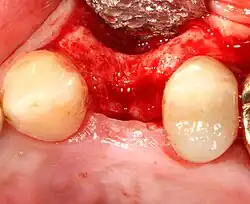

Спад десны приводит к обнажению металлического абатмента под зубной коронкой.